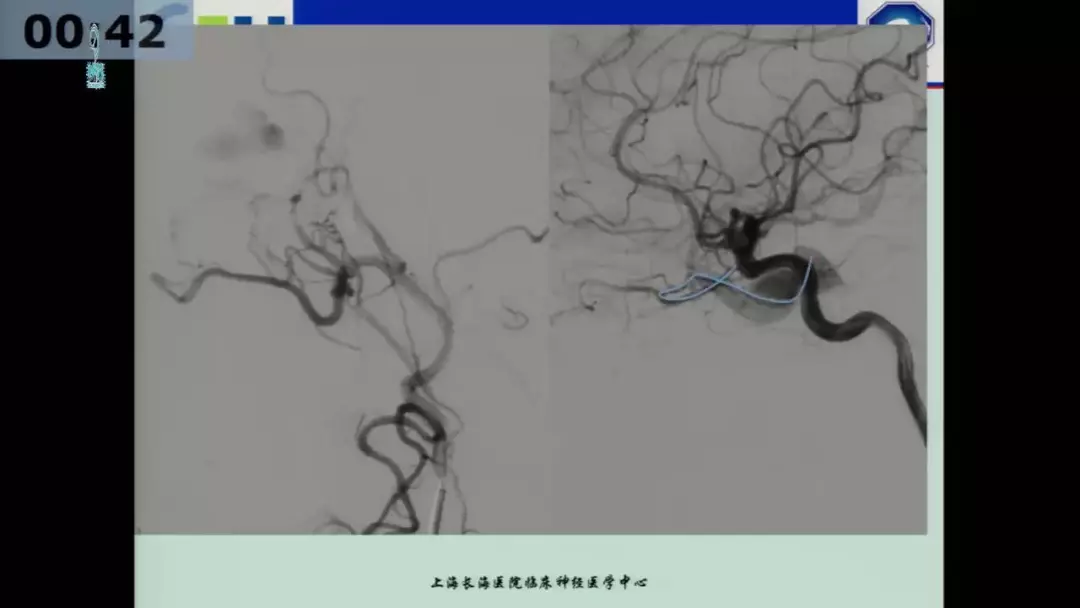

许奕教授:海绵窦区脑膜动静脉瘘的介入治疗